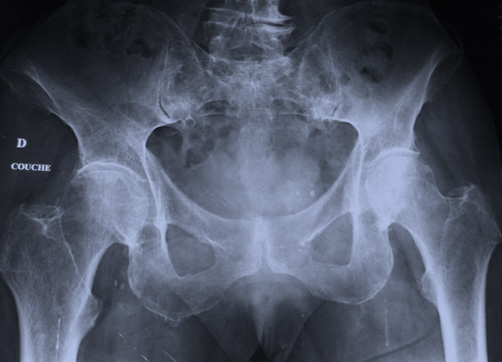

Mme C., 76 ans, a présenté une douleur violente du creux inguinal droit, lors d’une simple station debout dans sa cuisine. Elle a présenté, immédiatement, une impotence fonctionnelle complète, empêchant l’appui. Elle a réussi à téléphoner à sa fille et à une ambulance. Arrivée aux urgences, la radiographie ci-dessous est réalisée.

La radiographie est considérée comme normale et